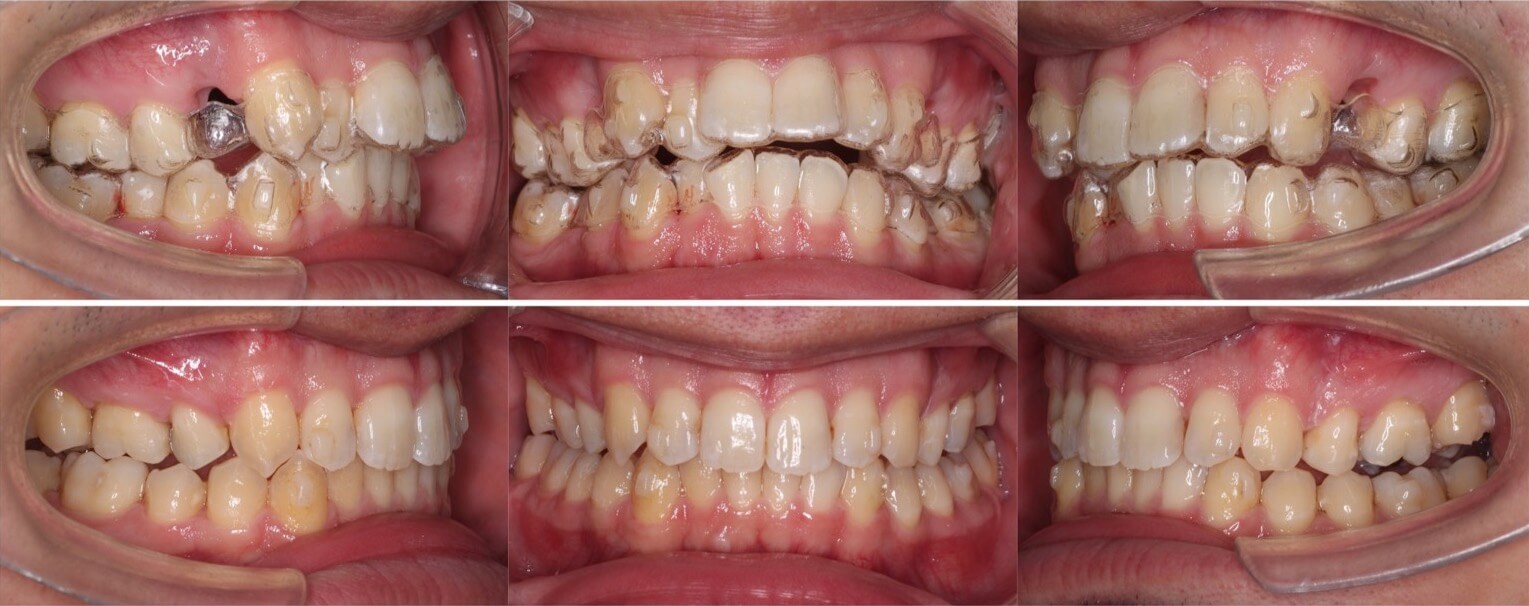

20代女性・ハーフリンガル装置・上下抜歯

上顎前突症に加えて、左側にシザースバイト(奥歯のすれ違い)症状もあるケースです。上の歯並びは裏側につける矯正装置のみでは対応できなかったため、奥歯のみ外側にブラケット矯正装置を装着しています。治療後は上の前歯が下唇にあたらなくなり、口が閉じやすくなりました。

<症例概要> 難易度:★★★★★

主訴:口元を引っ込めたい

年齢・性別:20代女性

住まい:千葉県八千代市

症状:下顎後退・上下顎前歯唇側傾斜・左側シザースバイト

治療方針:抜歯空隙の閉鎖(最大固定)

治療装置:ハーフリンガル矯正装置(上のみ裏側装置)

固定:歯科矯正用アンカースクリュー(口蓋側壁x2)

抜歯:上第一小臼歯・下第二小臼歯

治療期間:2年7か月

リテーナー:上下プレートタイプ+クリアタタイプ+フィックスタイプ

治療費用:1,320,000(税込)

代表的副作用:痛み・治療後の後戻り・歯根吸収・歯髄壊死・歯肉退縮

▶︎その他の副作用